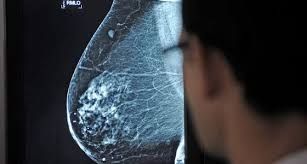

Una gran cantidad de mujeres no se hicieron la mamografía anual por miedo al covid

Entre el 40% y el 70% de las mujeres se ausentaron en sus controles anuales ginecológicos por temor a contagiarse de covid-19 desde marzo hasta octubre. A raíz de este fuerte dato, los gobiernos provinciales aprovecharon en el Día de Lucha contra el cáncer de mama que se conmemora hoy para recordar que las consultas habituales son imprescindibles para la detección temprana de patologías.